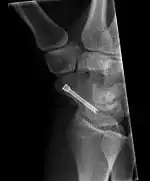

The scaphoid can be slow to heal because of the limited circulation to the bone. Fractures of the scaphoid must be recognized and treated quickly, as prompt treatment by immobilization or surgical fixation increases the likelihood of the bone healing in anatomic alignment, thus avoiding mal-union or non-union.[5] Delays may compromise healing. Failure of the fracture to heal ("non-union") will lead to post-traumatic osteoarthritis of the carpus.[1]:189 One reason for this is because of the "tenuous" blood supply to the proximal segment.[2] Even rapidly immobilized fractures may require surgical treatment, including use of a headless compression screw such as the Herbert screw to bind the two halves together.

Healing of the fracture with a non-anatomic deformity (frequently, a volar flexed "humpback") can also lead to post-traumatic arthritis. Non-unions can result in loss of blood supply to the proximal pole, which can result in avascular necrosis of the proximal segment.

Scaphoid fractures may be difficult to diagnose via plain x-ray, so repeat x-ray may be used at a later date, or cross-sectional imaging via MRI or CT scan.[5]